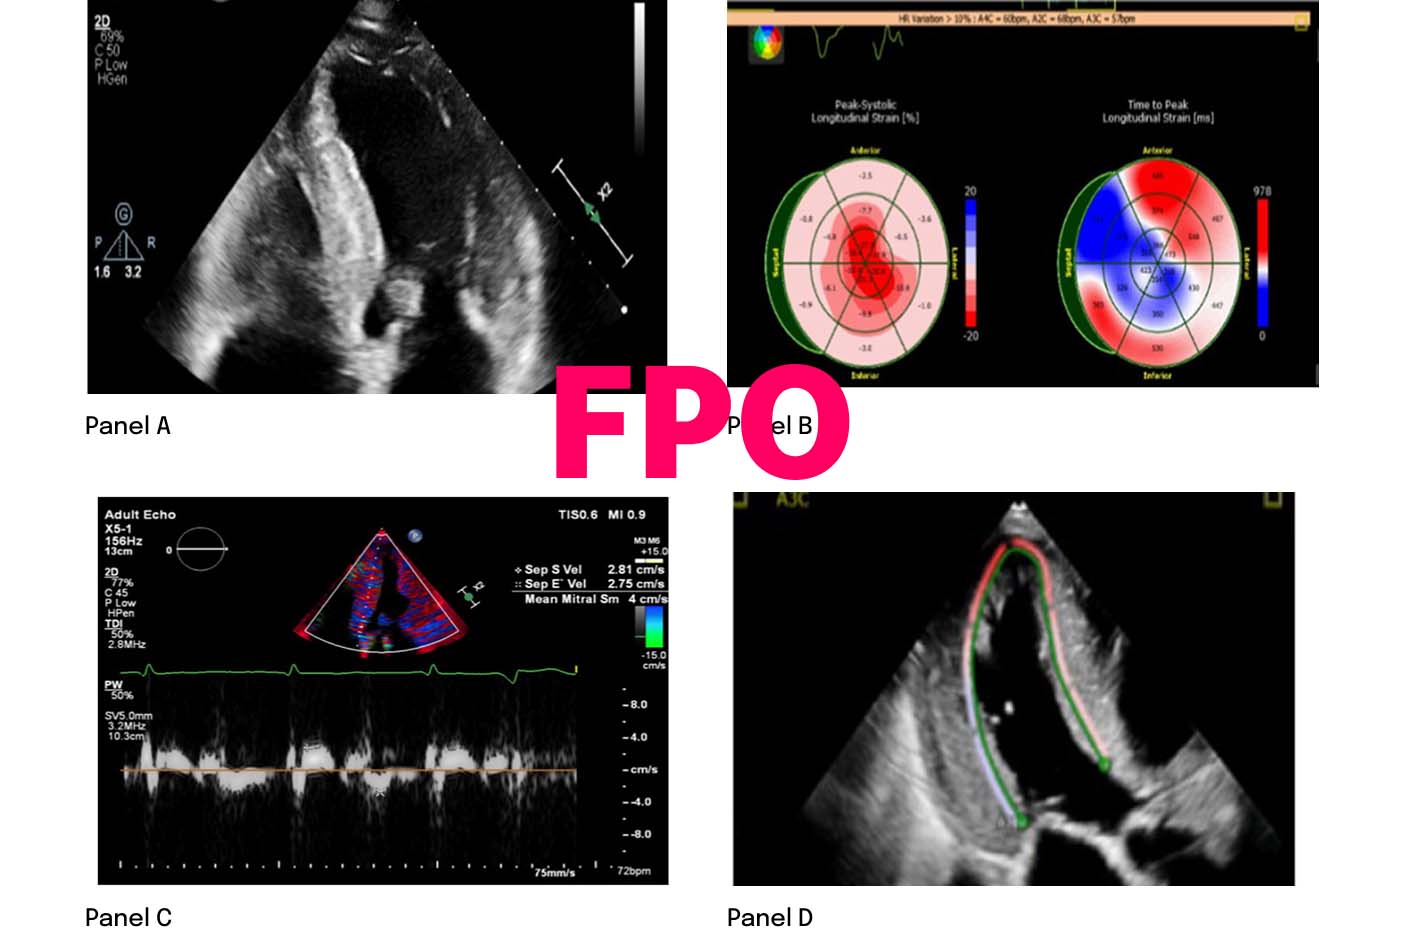

ECHO4

- Hypertrophic phenotype with infiltrative features

- Restrictive LV filling with RV wall thickening

- Low septal and lateral e′

- Reduction in global longitudinal strain